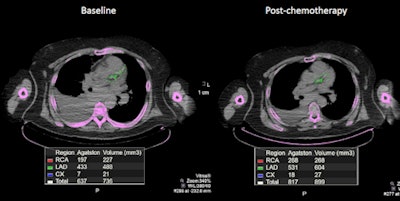

A 71-year-old man with non-Hodgkin's lymphoma had a total calcium score of 637 on his baseline PET/CT. When the scan was performed one year later after two cycles of chemotherapy, it showed a significant increase in calcium deposition and a calcium score of 817. Image courtesy of Dr. Ahmed El-Sabbagh.

A 71-year-old man with non-Hodgkin's lymphoma had a total calcium score of 637 on his baseline PET/CT. When the scan was performed one year later after two cycles of chemotherapy, it showed a significant increase in calcium deposition and a calcium score of 817. Image courtesy of Dr. Ahmed El-Sabbagh.Given the study's findings, oncologists and cardiologists at Saint Louis University are considering how to take advantage of coronary calcium scores generated by PET/CT scans. That information could be added to PET/CT reports to help evaluate the risk of cardiotoxicity in patients undergoing chemotherapy.